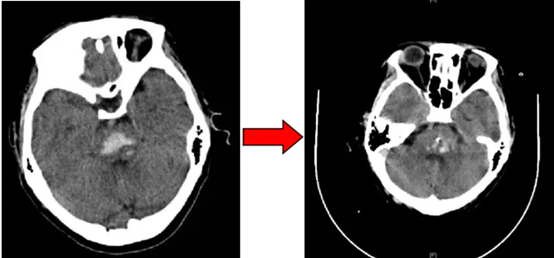

经过引流管的持续抽吸及引流,仅仅经过36个小时,患者颅内血肿被大部分清除。随后复查CT,可见血肿基本消失。术后第三天,患者已可自动睁眼,脱离呼吸机,恢复自主呼吸。